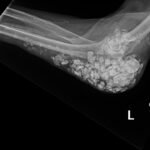

Calcinosis cutis is a condition in which calcium-phosphate salt deposits are formed in cutaneous and subcutaneous tissue. A subtype, metastatic calcinosis cutis, can occur in patients with disorders that cause hypercalcemia or hyperphosphatemia such as end stage renal disease. We present a case of a 67-year-old man with end-stage renal disease (ESRD) on dialysis who presented to the emergency department with a draining left elbow wound. On exam, he had irregular, firm nodules palpable in the subcutaneous tissue of both large and small joints. The presence of calcinosis cutis on imaging and lack of other findings suggesting infection led to outpatient wound care treatment. Recognizing the appearance of calcinosis cutis on imaging and conditions that present with calcinosis cutis is important for the emergency physician.